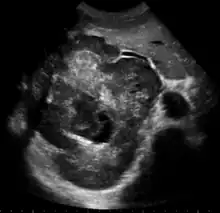

Ultrasound

Ultrasonography of liver tumors involves two stages: detection and characterization. Tumor detection is based on the performance of the method and should include morphometric information (three axes dimensions, volume) and topographic information (number, location specifying liver segment and lobe/lobes). The specification of these data is important for staging liver tumors and prognosis. Tumor characterization is a complex process based on a sum of criteria leading towards tumor nature definition. Often, other diagnostic procedures, especially interventional ones are no longer necessary. Tumor characterization using the ultrasound method will be based on the following elements: consistency (solid, liquid, mixed), echogenicity, structure appearance (homogeneous or heterogeneous), delineation from adjacent liver parenchyma (capsular, imprecise), elasticity, posterior acoustic enhancement effect, the relation with neighboring organs or structures (displacement, invasion), vasculature (presence and characteristics on Doppler ultrasonography and contrast-enhanced ultrasound (CEUS).